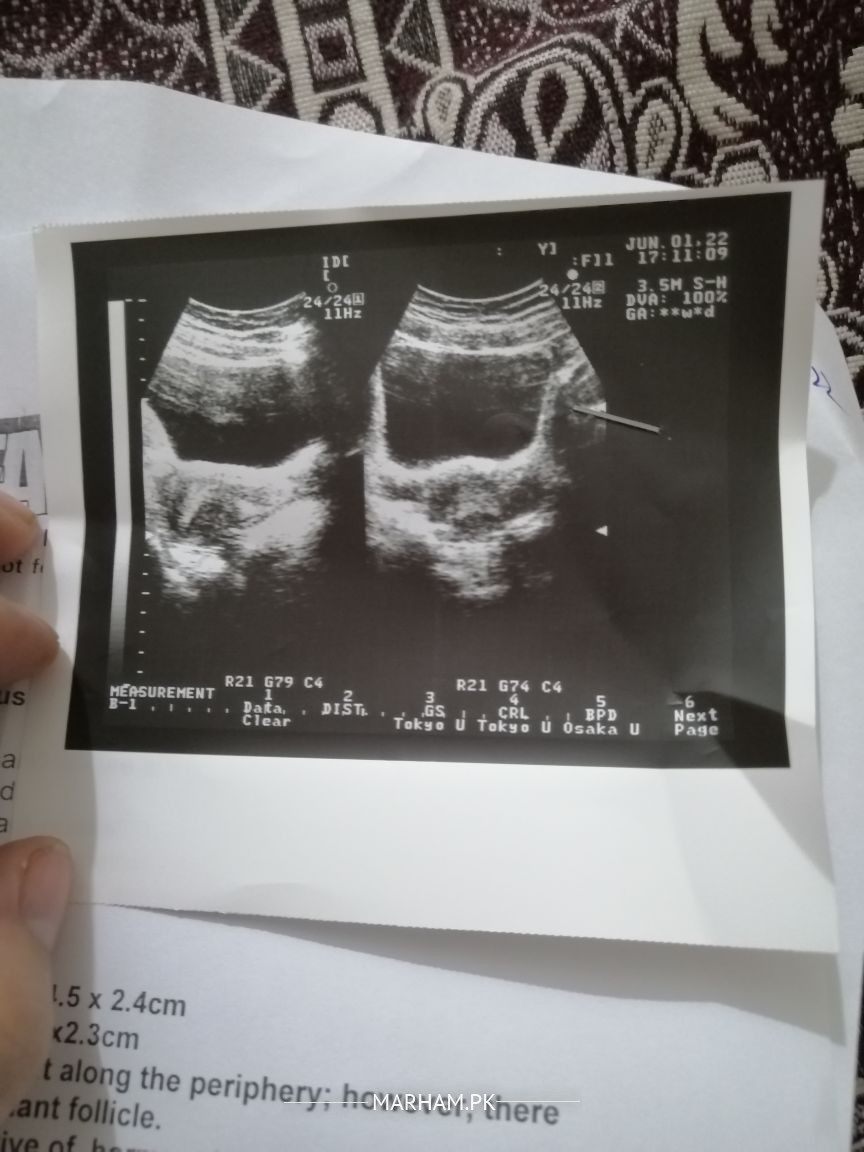

Attach Photo here: